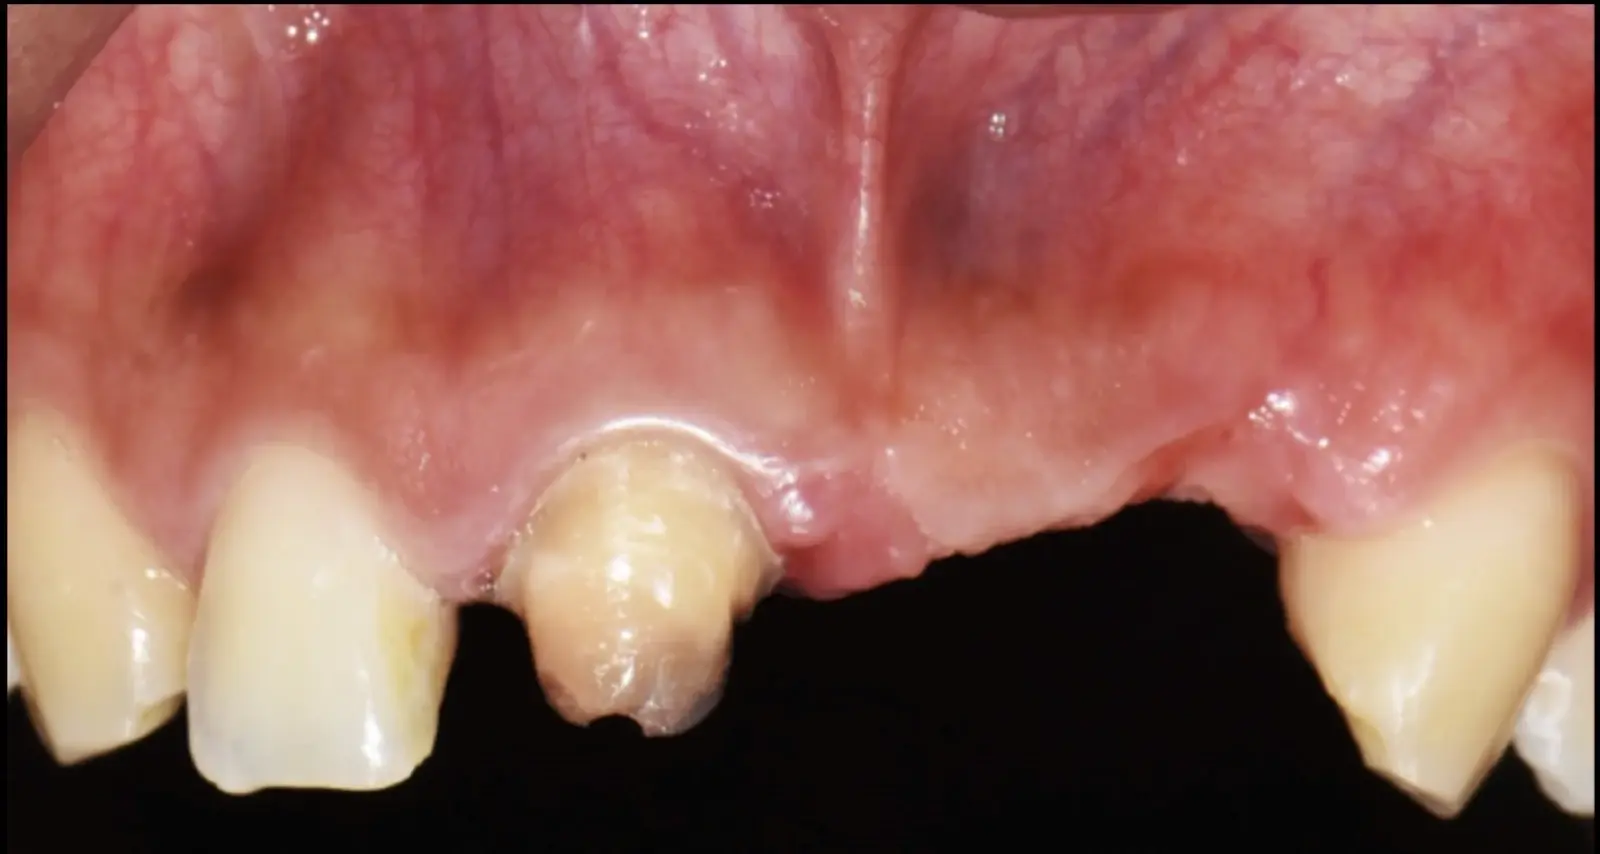

Figura 18. Vista clínica en la que se evidencia la deficiencia horizontal severa del reborde alveolar.

Paciente de sexo femenino de 36 años de edad, llega a la consulta por presentar una restauración protésica inadecuada. En el examen clínico se observa una restauración protésica provisional acrílica sobre las piezas 1.1 y 2.2. Adicionalmente, se aprecia recesión gingival a nivel de la pieza 2.2 y deficiencia horizontal severa de reborde a nivel de la zona edéntula correspondiente a la pieza 2.1. En la evaluación tomográfica se observa ausencia total de tabla ósea vestibular en la pieza 2.2, y se corrobora el déficit en la zona edéntula de la pieza 2.1, para lo cual se indica una reconstrucción de estructuras óseas con hueso en bloque de origen bovino y posteriormente la colocación de implantes dentales.

Figura 34. Vista frontal donde se observa deficiencia vertical del reborde óseo a nivel de las piezas 2.1, 2.2.